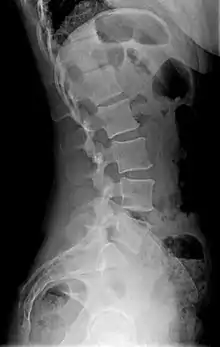

In radiology, a lordotic view is an X-ray taken of a patient leaning backward.[7]

X-ray

Precise diagnosis is done by looking at a complete medical history, physical examination, and other tests of the patient. X-rays are used to measure the lumbar curvature. On a lateral X-ray, a normal range of the lordotic curvature of between 20° and 60° has been proposed by Stagnara et al., as measured from the inferior endplate of T12 to the inferior endplate of L5.[18] The Scoliosis Research Society has proposed a range of 40° and 60° as measured between the upper endplate of Th12 and the upper endplate of S1.[18] Individual studies, although using other reference points, have found normal ranges up to approximately 85°.[18] It is generally more pronounced in females.[18] It is relatively constant through adolescence and young adulthood, but decreases in the elderly.[18]